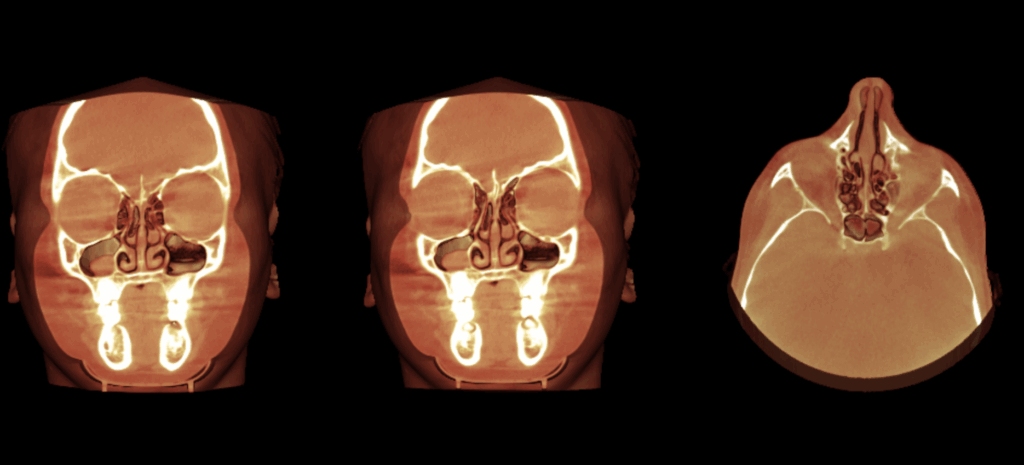

En las reconstrucciones 3D se representa de manera didáctica Concha Bullosa (Figura 4).

RECONSTRUCCIÓN 3D